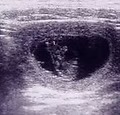

Echographe

Le cabinet est équipé d’un échographe portable doppler.

Pour une échographie abdominale, l’animal est couché sur le dos, le ventre est tondu et un gel est appliqué sur la peau afin d’assurer une bonne transmission des ondes.

L’échographie abdominale permet de rechercher des abcès (hépatiques par ex), des pyomètres (pus dans l’utérus), des cystopathies (maladie de la vésicule biliaire), des hyperplasies de la prostate…

Pour une échographie cardiaque, l’animal est debout. Cette échographie permet de mesurer l’épaisseur des parois du cœur, sa capacité à se contracter, de recherche des pathologies valvulaires…